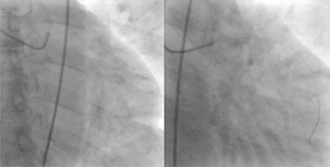

Een percutane coronaire interventie (PCI) – tot 2006 werd in de medische nomenclatuur gesproken van een percutane transluminale coronaire angioplastiek (PTCA) – is een angioplastiek, ook wel 'dotteren' genoemd, van een vernauwing (stenose) in een kransslagader.

De ingreep bestaat uit het met een hartkatheterisatie vergelijkbare procedure inbrengen van een ballonnetje en dat vervolgens op te blazen. Het bloedvat wordt zo opgerekt en kan weer voldoende bloed doorlaten. Vaak wordt daarbij tevens een stent geplaatst: een (meestal) stalen veertje met een bepaalde vorm dat in opgevouwen toestand wordt ingebracht en op de juiste plaats tot ontplooiing wordt gebracht. Het zorgt er voor dat het bloedvat open blijft. Problemen die na het plaatsen van een stent kunnen ontstaan, zoals de vorming van bloedstolsels op het lichaamsvreemde materiaal of het dichtslibben van het vat net naast de geplaatste stent zijn met medicatie grotendeels te voorkomen.